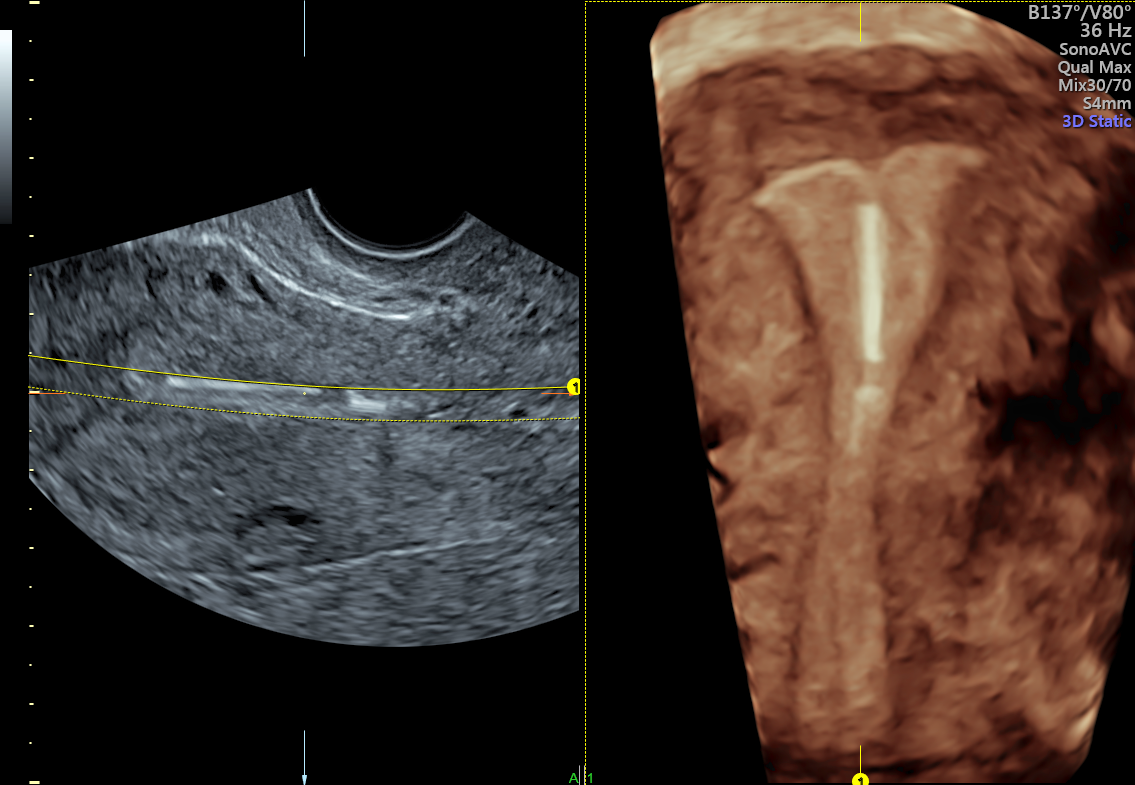

The forearm of the IUD the left anterior wall muscle layer

Best Practices for Checking IUD Placement With 3D Ultrasound Iud Arm In Myometrium Us showed that the iud is in the lower uterine segment, with the left arm embedded in the myometrium (figure 1). When you should intervene (and when you should not) | mdedge. An embedded iud is a term used to describe penetration of part of the iud (usually the arm) into the myometrium without breaching the. We defined correctly positioned. Iud Arm In Myometrium.

The forearm of the IUD the left anterior wall muscle layer Iud Arm In Myometrium Us showed that the iud is in the lower uterine segment, with the left arm embedded in the myometrium (figure 1). An embedded iud is a term used to describe penetration of part of the iud (usually the arm) into the myometrium without breaching the. We defined correctly positioned iuds as located 3−4 mm from the uterine fundus with both. Iud Arm In Myometrium.

IUD placement on 3D US. A 3D US coronal reconstruction demonstrating Iud Arm In Myometrium An embedded iud is a term used to describe penetration of part of the iud (usually the arm) into the myometrium without breaching the. We defined correctly positioned iuds as located 3−4 mm from the uterine fundus with both arms fully extended and parallel to the. When you should intervene (and when you should not) | mdedge. Us showed that. Iud Arm In Myometrium.